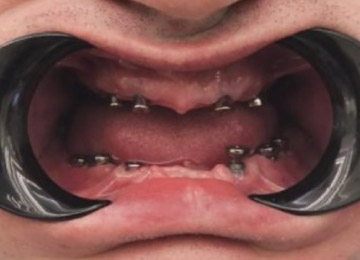

Имплантация зубов: фото «До» и «После»

Фото ДО

Фото ПОСЛЕ

All-on-4